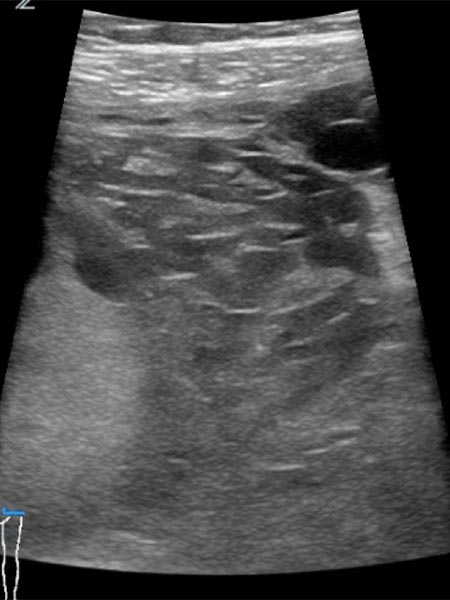

Pre-pregnancy ultrasound imaging with 10.4 MHz linear transducer. Evidence of an intramuscular subfascial venous malformation with multiple hypoechoic venous channels.